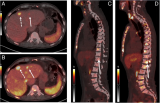

钇[90Y]炭微球注射液是选择性内照射治疗(SIRT)用放射性微球,是以炭微球为载体负载高活度的放射性钇[90Y]而得,通过DSA介入手术经肝动脉灌注至肿瘤供血动脉。钇[90Y]炭微球随血流分布并阻滞于肿瘤组织微小动脉和毛细血管中,钇[90Y]发射纯β射线,平均能量为0.9367MeV,平均组织穿透距离为2.5mm,最终通过选择性内照射治疗杀死肿瘤细胞达到治疗目的。 2023-03-28 放射诊疗靶向治疗